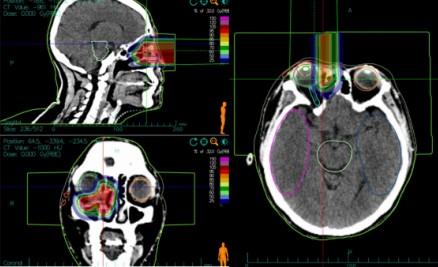

With years of clinical experience and superb heavy ion therapy technology, Director Li Xiaojun developed an individualized heavy ion therapy treatment plan for the patient. On July 20, 2022, the patient underwent carbon ion radiotherapy (uniform scanning). Because the tumor was adjacent to important organs such as the eyeball and optic nerve, a two-stage treatment plan was designed to further increase the radiation dose to the tumor area and reduce the dose to critical organs.

The first-stage plan treated the tumor and subclinical areas. The patient was positioned in the lateral decubitus position, and two horizontal fields were irradiated at couch angles of 0° and 325°.

The second-stage plan targeted the residual tumor area. The patient was positioned in the supine position, and a vertical field was used for irradiation to protect the eyeball.

Figure 1: Case 1 – Dose Distribution Map of Carbon Ion Therapy for a Patient with Lacrimal Sac Squamous Cell Carcinoma (First Course)

Figure 1: Case 1 – Dose Distribution Map of Carbon Ion Therapy for a Patient with Lacrimal Sac Squamous Cell Carcinoma (Second Course)